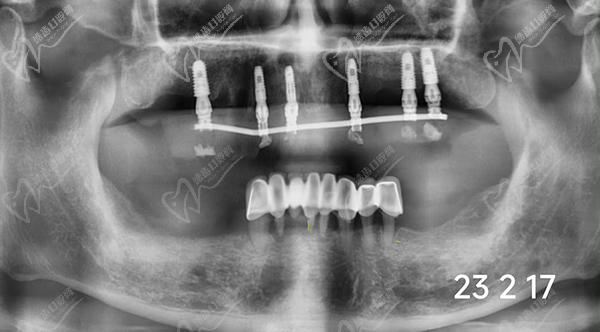

牙友1、前天結(jié)束的全口種植牙,拔牙加同期種12顆瑞士士卓曼,即刻負(fù)重!全口牙周炎伴隨多顆牙松動且骨量不足等問題,普通的種植手術(shù)無法滿足生活需求,想要做即拔即種即刻戴上臨時(shí)牙,因?yàn)槌R?guī)的植骨手術(shù)需要等待很長時(shí)間。經(jīng)過正規(guī)醫(yī)院骨質(zhì)評估分析,上頜AO4+兩邊穿翼手術(shù),患者手術(shù)結(jié)束當(dāng)天就可以正常用牙,本人表示非常高興和滿意!感謝醫(yī)院團(tuán)隊(duì)協(xié)作!

圖是我的臨時(shí)牙冠,即拔即種的牙冠都是臨時(shí)的,后期要來重新裝